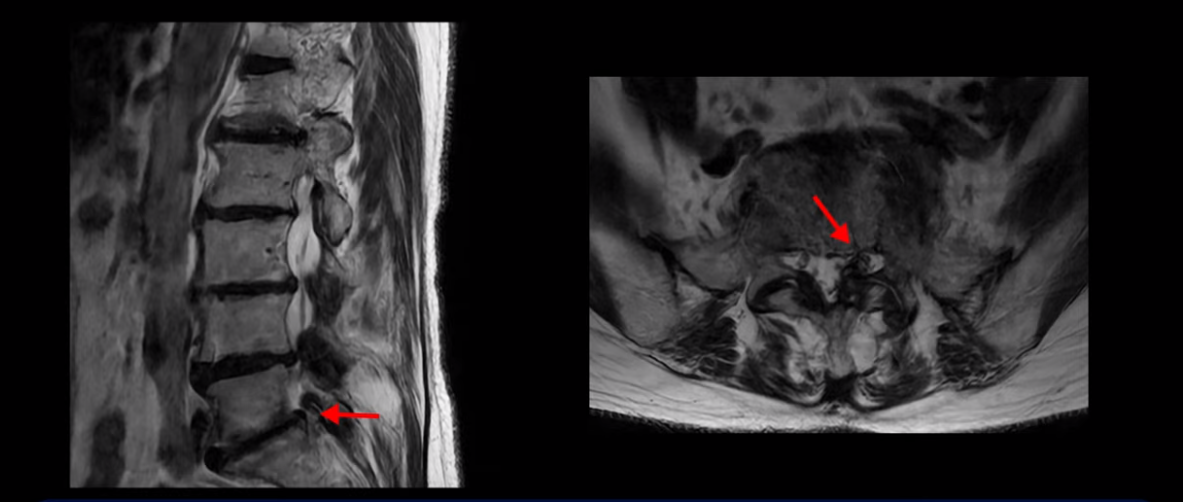

이분 MRI를 보고 설명해 드린 후 어떻게 허리 여러 마디에서 신경이 심하게 눌려 보이는 협착증 환자가 수술 없이 좋아질 수 있는지, 또 치료는 어떻게 하는지 설명해 드리겠습니다.

이분 MRI 보시다시피 허리 다섯 마디가 전부 다 퇴행이 심합니다.

특히 4번 5번에는 심한 중심성 협착이 있고,

5번 1번에는 황색인대가 골화되어 왼쪽 신경 나가는 길이 좁아져 있습니다.

그래서 왼쪽 엉덩이와 다리 통증이 더 심합니다. 이렇게 신경 구멍들이 좁아져 있고 신경이 눌리니까 엉덩이와 다리가 너무 저리고 아프고 힘도 빠져서 몇 걸음도 걷기 어려우니까 지팡이를 짚고 저녁에도 아파서 잠을 못 자는 겁니다.